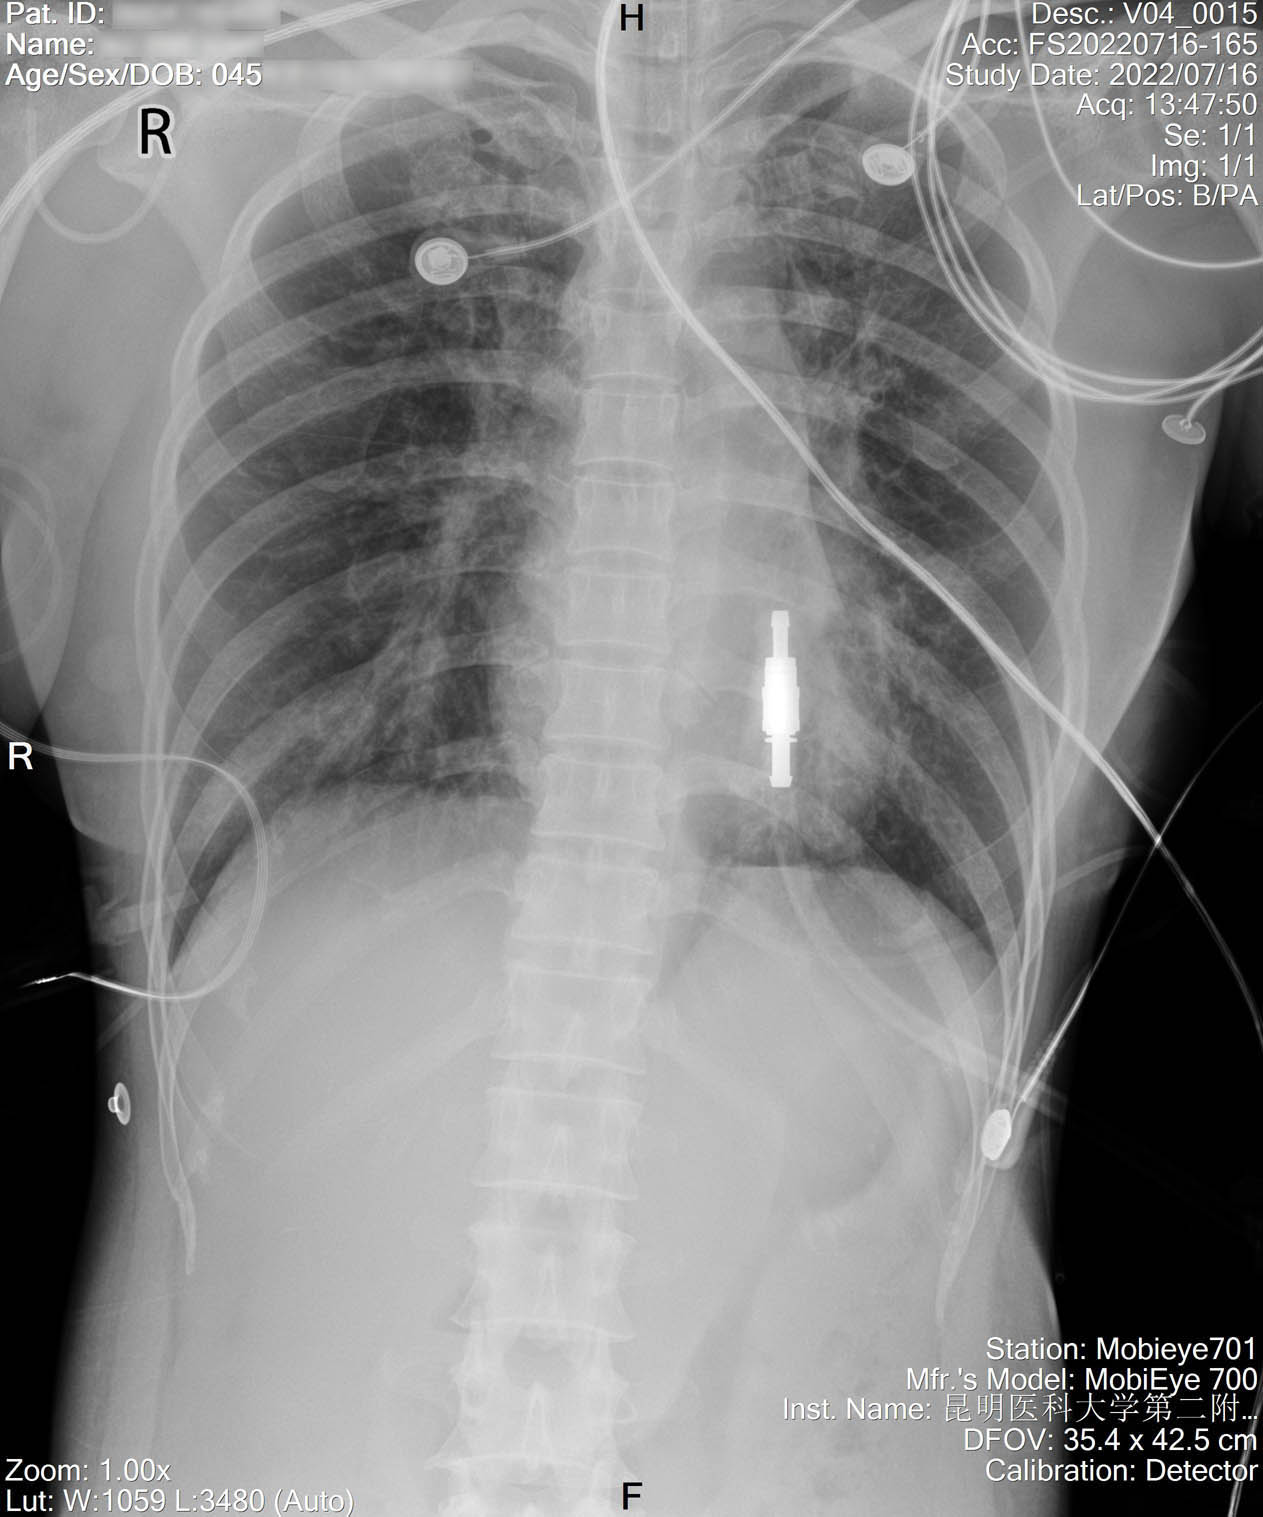

2022-07-16_胸片